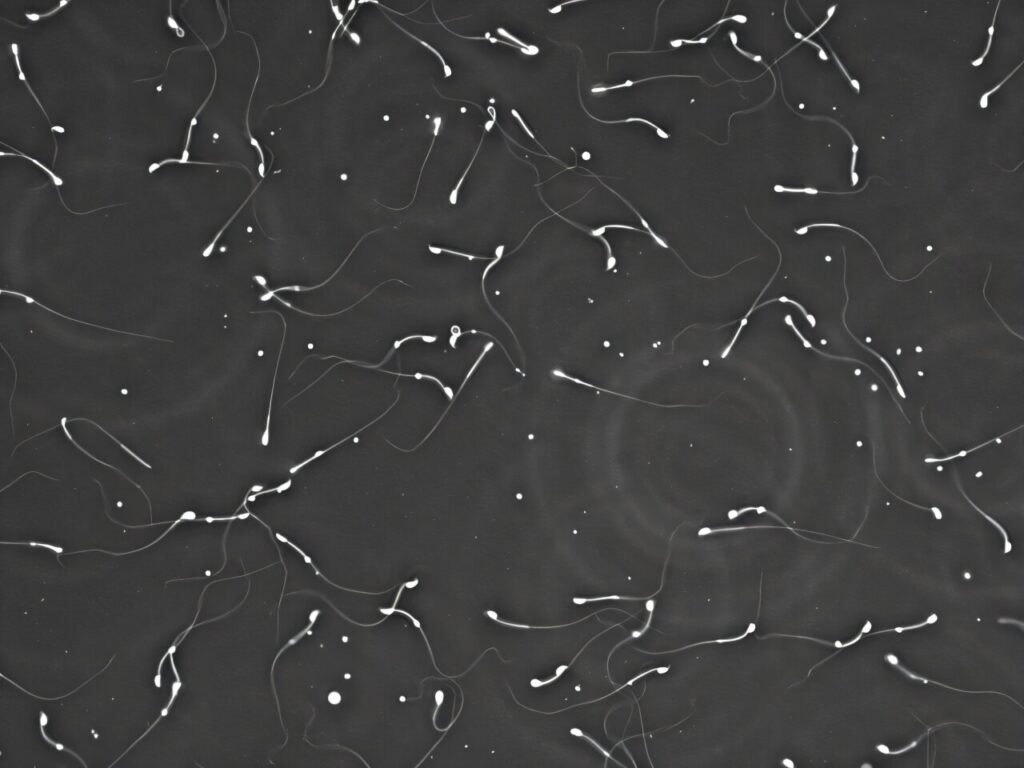

– A decrease in developing sperm count during the PFAS exposure period.

– Despite these changes, sperm retained normal function in laboratory conditions.

According to Professor Nixon, the study showed that PFAS exposure at environmentally relevant levels can lead to molecular changes in sperm, even though they may appear normal on the surface. The research also observed lower testosterone and DHT levels in male mice exposed to PFAS, along with a decrease in daily sperm production.

The study’s results align with previous human studies linking high PFAS exposure to lower sperm counts in men. The researchers emphasized the importance of understanding how PFAS exposure affects reproductive health and future generations, especially in communities like Williamtown where PFAS contamination is a pressing issue.